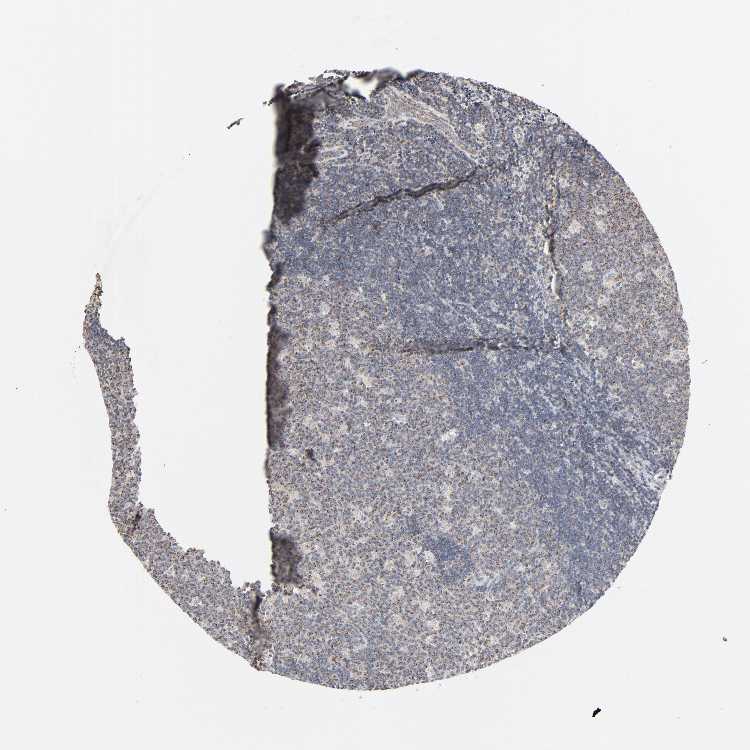

LYMPH NODE - Antibody stainingi

Antibody staining in the annotated cell types in the current human tissue is reported as not detected, low, medium, or high, based on conventional immunohistochemistry profiling in selected tissues. This score is based on the combination of the staining intensity and fraction of stained cells.

Each image is clickable and will lead to virtual microscopy that enables deeper exploration of all samples and also displays staining intensity scores, fraction scores and subcellular localization as well as patient and tissue information for each sample.

Antibody HPA004199Antibody HPA076871

Germinal center cells MediumNot detected

Non-germinal center cells LowNot detected